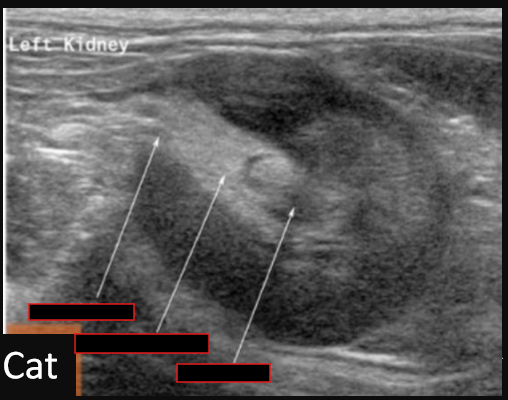

Identify the kidneys What pathology is present?

Identify this structure What pathology is present?

Label this structure What pathology is present?